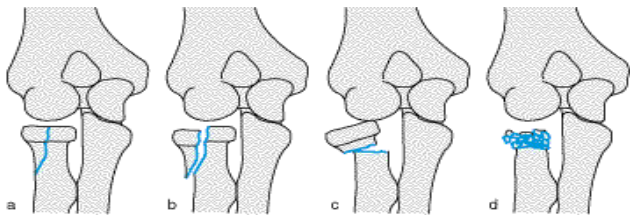

Epiphysen(Wachtumszonen)fraktuen nach Aitken - körperferne Tibia (Schienbein)

a) Aitken 0

Epiphysen-Lösung

b) Aitken 1

Fraktur am körpernahen Anteil

c) Aitken 2

Fraktur körperferner Anteil

Epiphyse evtl. mit abgebrochen

d) Aitken 3

Fraktur: körpernaher/körperferner Anteil

Beide teile ober/unterhalb Epiphyse ab